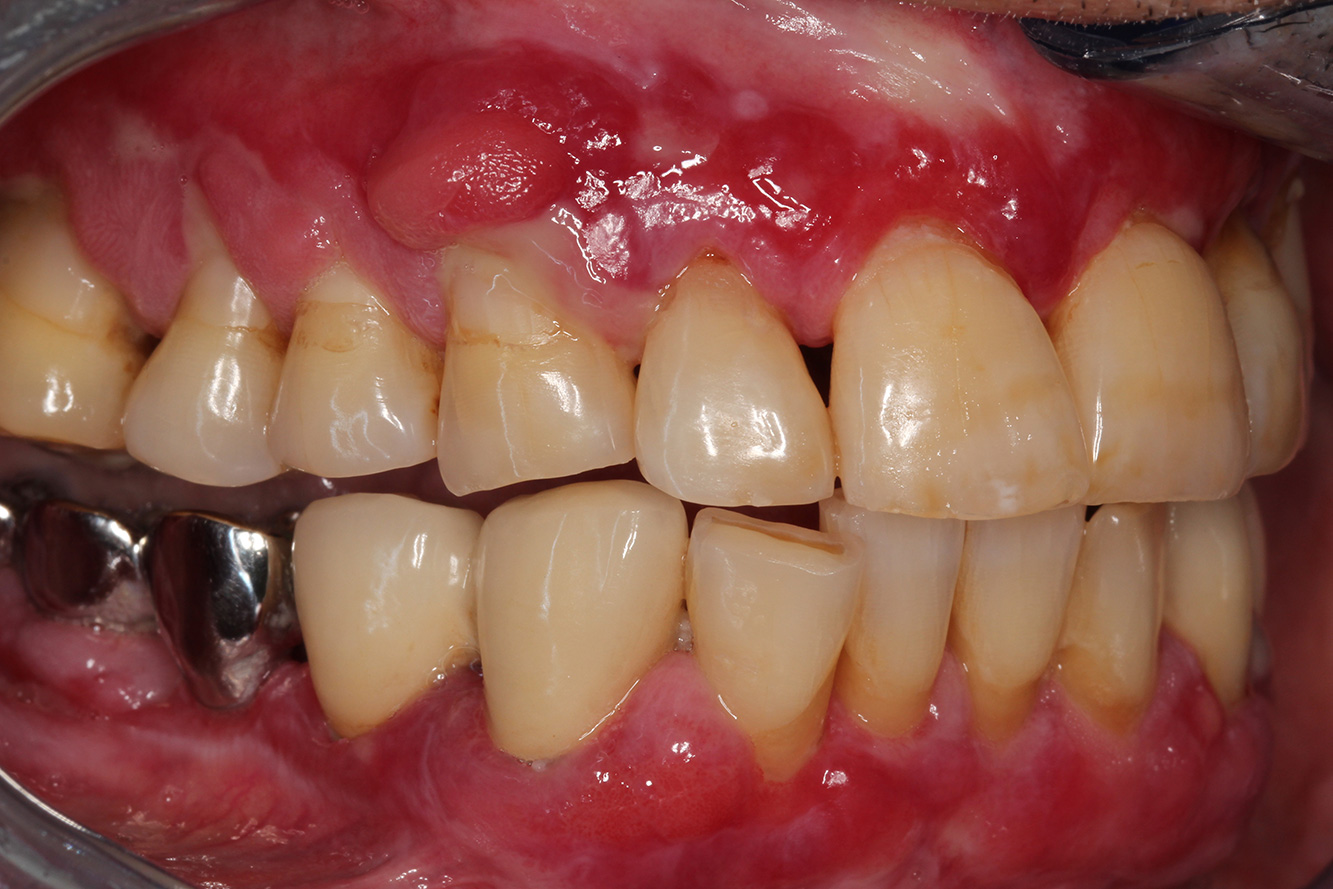

Se presenta un paciente de 71 años con trasplante de riñón e hipertensión (presión arterial alta). Debido a su historia médica, es necesario el tratamiento continuo con ciclosporina para suprimir el sistema inmunitario y amlopidina para bajar la presión arterial. Además, el paciente relata encías sensibles y sangrantes. Desde el punto de vista de la salud oral, hay dientes restaurados con ocho piezas faltantes, hiperplasia gingival pronunciada, periodontitis en fase II, de grado B con bolsas activas y una caries inicial en la pieza 22. En la evaluación del riesgo de caries se ha establecido un riesgo de caries medio (API 60). Para la sesión de profilaxis se hacen las siguientes recomendaciones.

Con base en la historia médica, se detecta un riesgo de complicaciones importante. Debido al trasplante de riñón, el paciente está inmunodeprimido (ciclosporina), también tiene el sistema inmunitario debilitado y necesita profilaxis para infecciones (recomendación: 2 g de amoxicilina como antibiótico 1 h antes de la sesión). Al mismo tiempo, el tratamiento continuo hace que el paciente tenga un mayor riesgo de enfermedad, dado que la hiperplasia gingival establecida está asociada a la medicación (20).

Se debe abordar la situación del paciente, especialmente cuando se trata de motivación y aprendizaje. La hiperplasia gingival dificulta la higiene oral en casa. La mayor susceptibilidad a las infecciones y el progreso y la nueva formación de hiperplasias (22) debe hablarse de igual a igual. Al mismo tiempo, deben explicarse las técnicas de higiene adecuadas según las necesidades individuales.

No hay recomendaciones específicas para la limpieza. Según el grado de conocimiento, debe hacerse el pulido rotativo de forma selectiva en zonas sensibles a la erosión. Precisamente porque la salud oral del paciente es frágil, es importante crear las mejores condiciones posibles para el mantenimiento en casa en la sesión de profilaxis, por ejemplo, creando superficies lisas, fluorizando para prevenir las caries y con enjuague bucal con clorhexidina para las inflamaciones activas.

Para el paciente se recomienda un intervalo de control posterior más corto, de tres a cuatro meses. Esto se debe principalmente a la hiperplasia gingival asociada a la medicación, la situación de cuidado difícil asociada y el alto riesgo de progresión de la periodontitis.